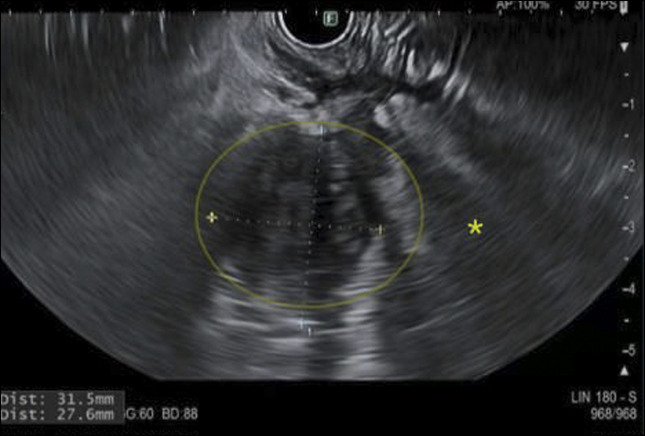

Vermiform appendiceal cancers are rare and commonly diagnosed incidentally after appendectomy for acute appendicitis. Establishing a diagnosis and staging appendiceal cancer is important as the treatment options differ based on the subtypes of tumor and their spread in the peritoneum. The role of endosonography in tissue diagnosis of appendiceal cancer is limited. Most cases are diagnosed and staged radiologically and surgically. Tissue diagnosis is key in management, especially when diagnosis is unclear by other modalities. We report a case of transduodenal endoscopic ultrasound-guided biopsy of an appendiceal lesion, which had significant impact on patient outcome.